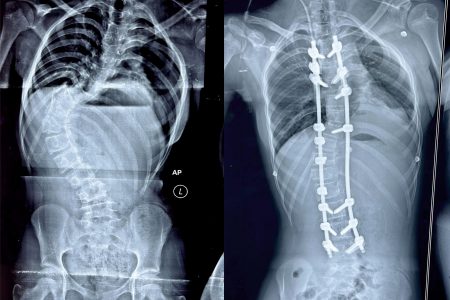

Kalinga Institute of Medical Sciences (KIMS), Bhubaneswar has successfully given a new lease of life to a teenage girl from Bhadrak, who was battling a spinal deformity known as Scoliosis. The abnormal curve in her spine gave it an ‘S-shaped’ appearance, threatening her promising future. However, thanks to the expertise of the doctors at KIMS, her spine was meticulously corrected in a recent complex operation, and she is now on the path to a full recovery, ready to embrace a normal life once again.

Dr. Rout explained that the spinal deformity the girl suffered from is known as “idiopathic scoliosis,” a condition that typically develops between the ages of 10 and 15 and if left untreated, can lead to severe deformities and significantly impact self-confidence and self-esteem. Such patients often become targets of ridicule due to their appearance. Correcting the deformity at an early age is crucial, as it becomes more challenging to treat an advanced age.

Notably, Dr. Rout, who is also the Secretary of the Spine Society of Odisha, accomplished the challenging operation in an impressive four hours, a procedure that typically takes 7-8 hours. The success of the surgery was further aided by the use of an advanced ‘intraoperative neuro monitoring’ machine, which promptly alerts the doctors to any potential complications during the procedure.